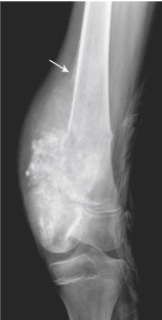

Osteoid Osteoma X-ray

Target-like radiolucent lesion (actual tumor or nidus which may be centrally mineralized) which is sharply demarcated with surrounding rim of thick/dense reactive cortical bone